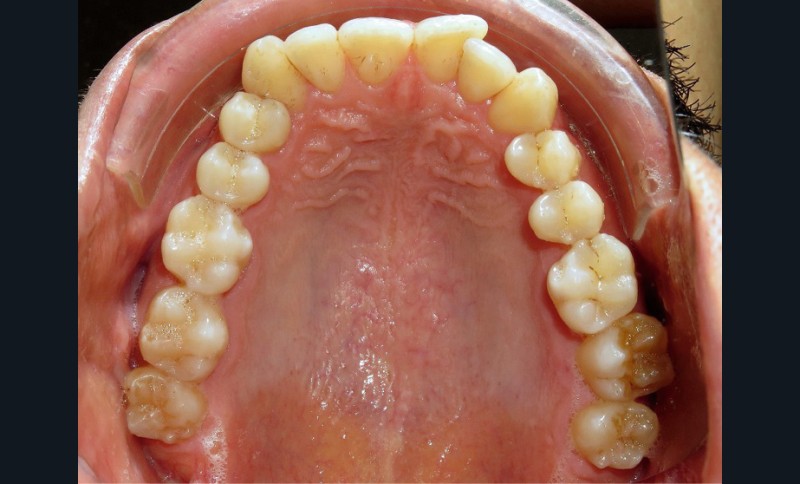

Diagnostic (fig. 1a-i)

Le patient consulte initialement pour des défauts d’alignement. L’examen clinique confirme l’existence d’un encombrement antérieur bimaxillaire, mais révèle aussi la présence d’une Classe II dentaire sévère, d’une exoclusion de la 27 et de troubles parodontaux (peu ou absence de papilles inter-dentaires). Sur le plan squelettique, le patient est relativement équilibré avec un profil harmonieux.